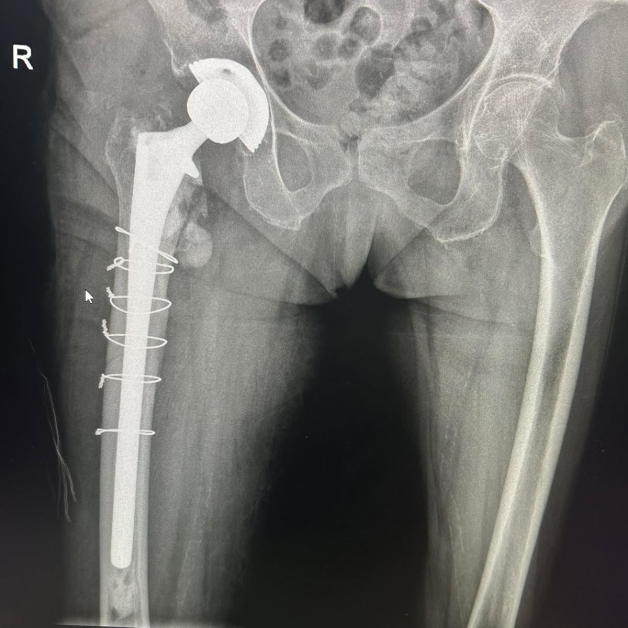

Животът на 80-годишна жена беше избавен след незабавна и сполучлива интервенция в Университетската многопрофилна болница за интензивно лекуване Каспела в Пловдив. Пациентката е с изкуствена тазобедрена става, сложена преди 7 години, само че след рухване е получила съществено строшаване на бедрената кост тъкмо под импланта.

Случаят е извънредно комплициран, защото костните фрагменти са били рисково покрай огромни кръвоносни съдове. Това е наложило незабавна хирургична интервенция.

Екипът на болничното заведение, отпред с доктор Димитър Генов и с присъединяване на доктор Благойчо Постоловски, е направил интервенцията бързо и точно. Използвано е особено ревизионно стебло, серклаж и циментна фиксация, с цел да се обезпечи непоклатимост на крайника.